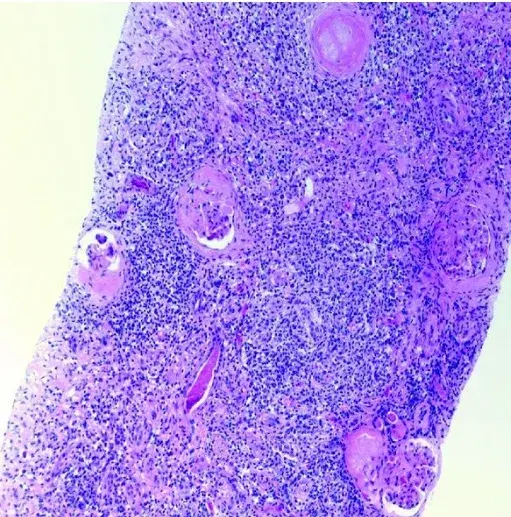

Proteinúria refratária em paciente com Nefrite Lúpica

Caso muito ilustrativo publicado no Kidney 360 (link) Paciente do sexo feminino com 43 anos e com antecedente de nefrite lúpica (NL) proliferativa há 13 anos. A paciente apresentava histórico de acometimento grave da doença, com múltiplos tratamentos com infusões de metilprednisona e ciclofosfamida devido ao acometimento do sistema nervoso central (SNC) e da NL.